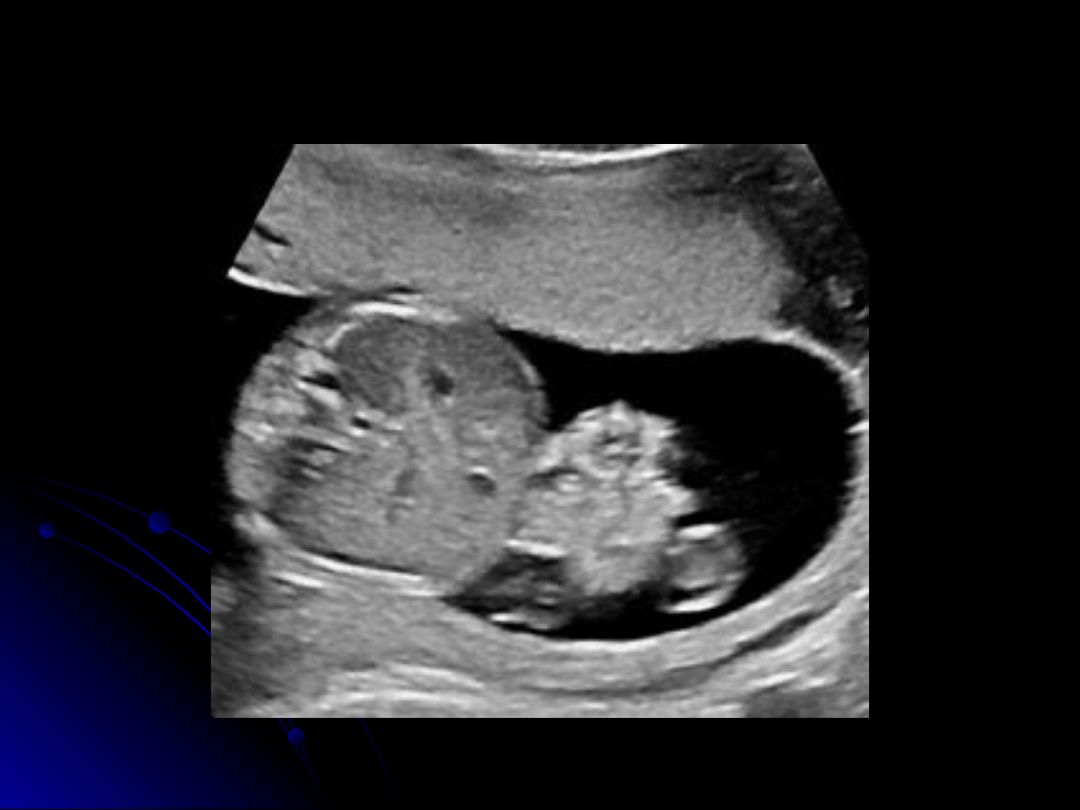

In the ultrasound image, which vessel is identified as the largest within the umbilical cord?